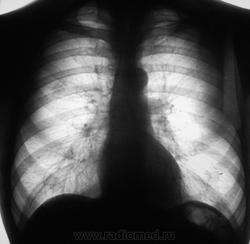

если не ошибаюсь добавочная доля v.azygos?ну и по воводу участка затемнения архиы бы глянуть.и узнать бы сосотояние на момент когда делала флюшку.

На момент производства "флюшки" жалоб нет.

На предыдущей "флюшке" (двухлетней давности) "этого" нет, норма.

Тогда будем диффиренцировать C-r и Tвс. У Вас, видимо, и боковая имеется, и томограммы припрятаны?

Необходимо дообследование ( боковая + т\графия)

Это выставлена флюшка за 2011 год.

В 2013 году пациент проходил профилактическую флюорографию в соседнем районе. Знаю одно, что пациента вызывали на доообследование, но он на дообследование не явился..., вот такие, вот дела...

В 2014 году пациент был направлен на профилактическую флюорографию и попал к нам.

В плане дообследования был сделан стандарт.